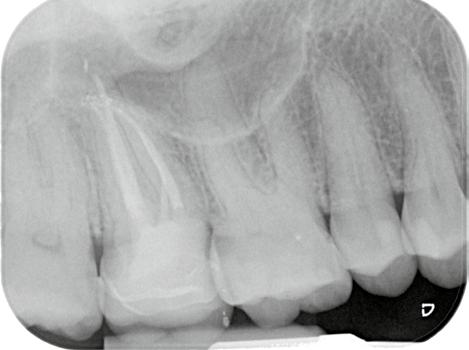

16. ábra: A kezelés közben készült felvétel. Az endodonciai csonkfelépítés már befejeződött, a hozzáférési nyílás kialakításra került és a csatornák előzetes feltágítása is megtörtént. A fogbélkamra alján jól megfigyelhető a transzlucensebb optikai tulajdonságokkal rendelkező pulpakő jelenléte. – 17. ábra: A pulpakövet kézi exkavátorral emeltük ki az üregből. 18. ábra: Az eltávolított pulpakő. – 19. ábra: A pulpakamra alja a gyökértömés elkészítését követően. A pulpakő eltávolítása után a fogbélkamra alja sokkal opakabb képet mutat.

20. ábra: Posztoperatív röntgenfelvétel.

21. ábra: Kiindulási felvétel. Az elhalt felső nagyőrlőfog rágás során panaszokat okoz a páciens számára. A felvételen jól látható a gyökércsatorna-rendszer beszűkültsége.

22. ábra: A hozzáférési nyílás kialakítását követően láthatóvá vált a fényes és kalcifikálódott dentinréteg. – 23. ábra: A kalcifikálódott terület vizsgálata során két gyökércsatorna-bemenet pozícióját sikerült lokalizálni. A kalcifikálódott szöveteket el kell távolítani a csatornák további tágítása előtt. – 24. ábra: A kalcifikálódott szövetek eltávolítását 15/.04-es MicroOpenerrel végeztük. A kalcifikáció néhány milliméter mélyen a palatinális csatornába is beterjedt. – 25. ábra: A pulpakamra aljának képe a csatornák feltágítását követően. A pulpakő eltávolítását követően helyreállt a fogbélkamra aljának megszokott opak megjelenése.

33. ábra: Posztoperatív felvétel.

26. ábra: Posztoperatív röntgen.